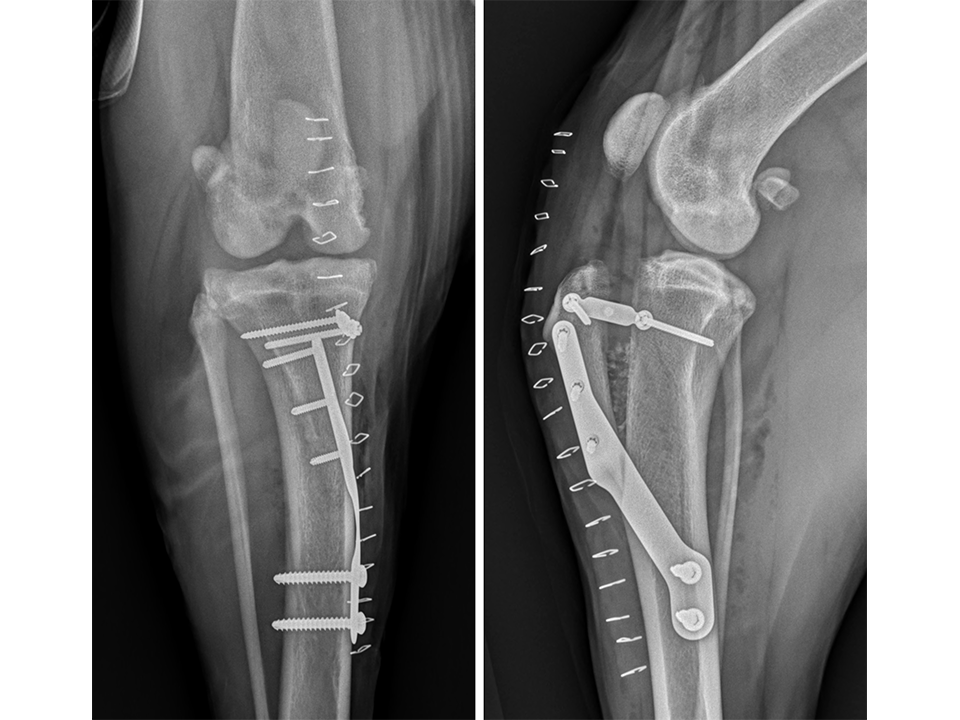

Immediate postoperative radiographs (Fig 7) revealed satisfactory implant and osteotomy positioning. Radiographs obtained 10 weeks postoperatively (Fig 8) showed no evidence of implant-associated complications and partial bone healing within the osteotomy gap. Osteoarthritic changes within the joint were static. Clinically at this stage, mild bilateral pelvic limb lameness was apparent bilateral stifle joint effusion. The left stifle joint was stable in CrTT with no pain response upon stifle joint manipulation.

The patient presented again 11 months postoperatively for assessment of right pelvic limb lameness associated with CrCL rupture. At this stage severe right pelvic limb lameness was evident but no lameness of the left pelvic limb was observed. While the right stifle joint was unstable in cranial drawer and CrTT, the left stifle remained stable with no pain response upon palpation over the implants and a normal range of motion of the joint. Radiographs of the previously operated left stifle (Fig 9) revealed no implant-associated complications and healing of the osteotomy. The osteoarthritic changes were static radiographically. TTA was performed on the right tibia at this time using a 13.5 mm wedge and a size 6 plate as had been used on the left previously.